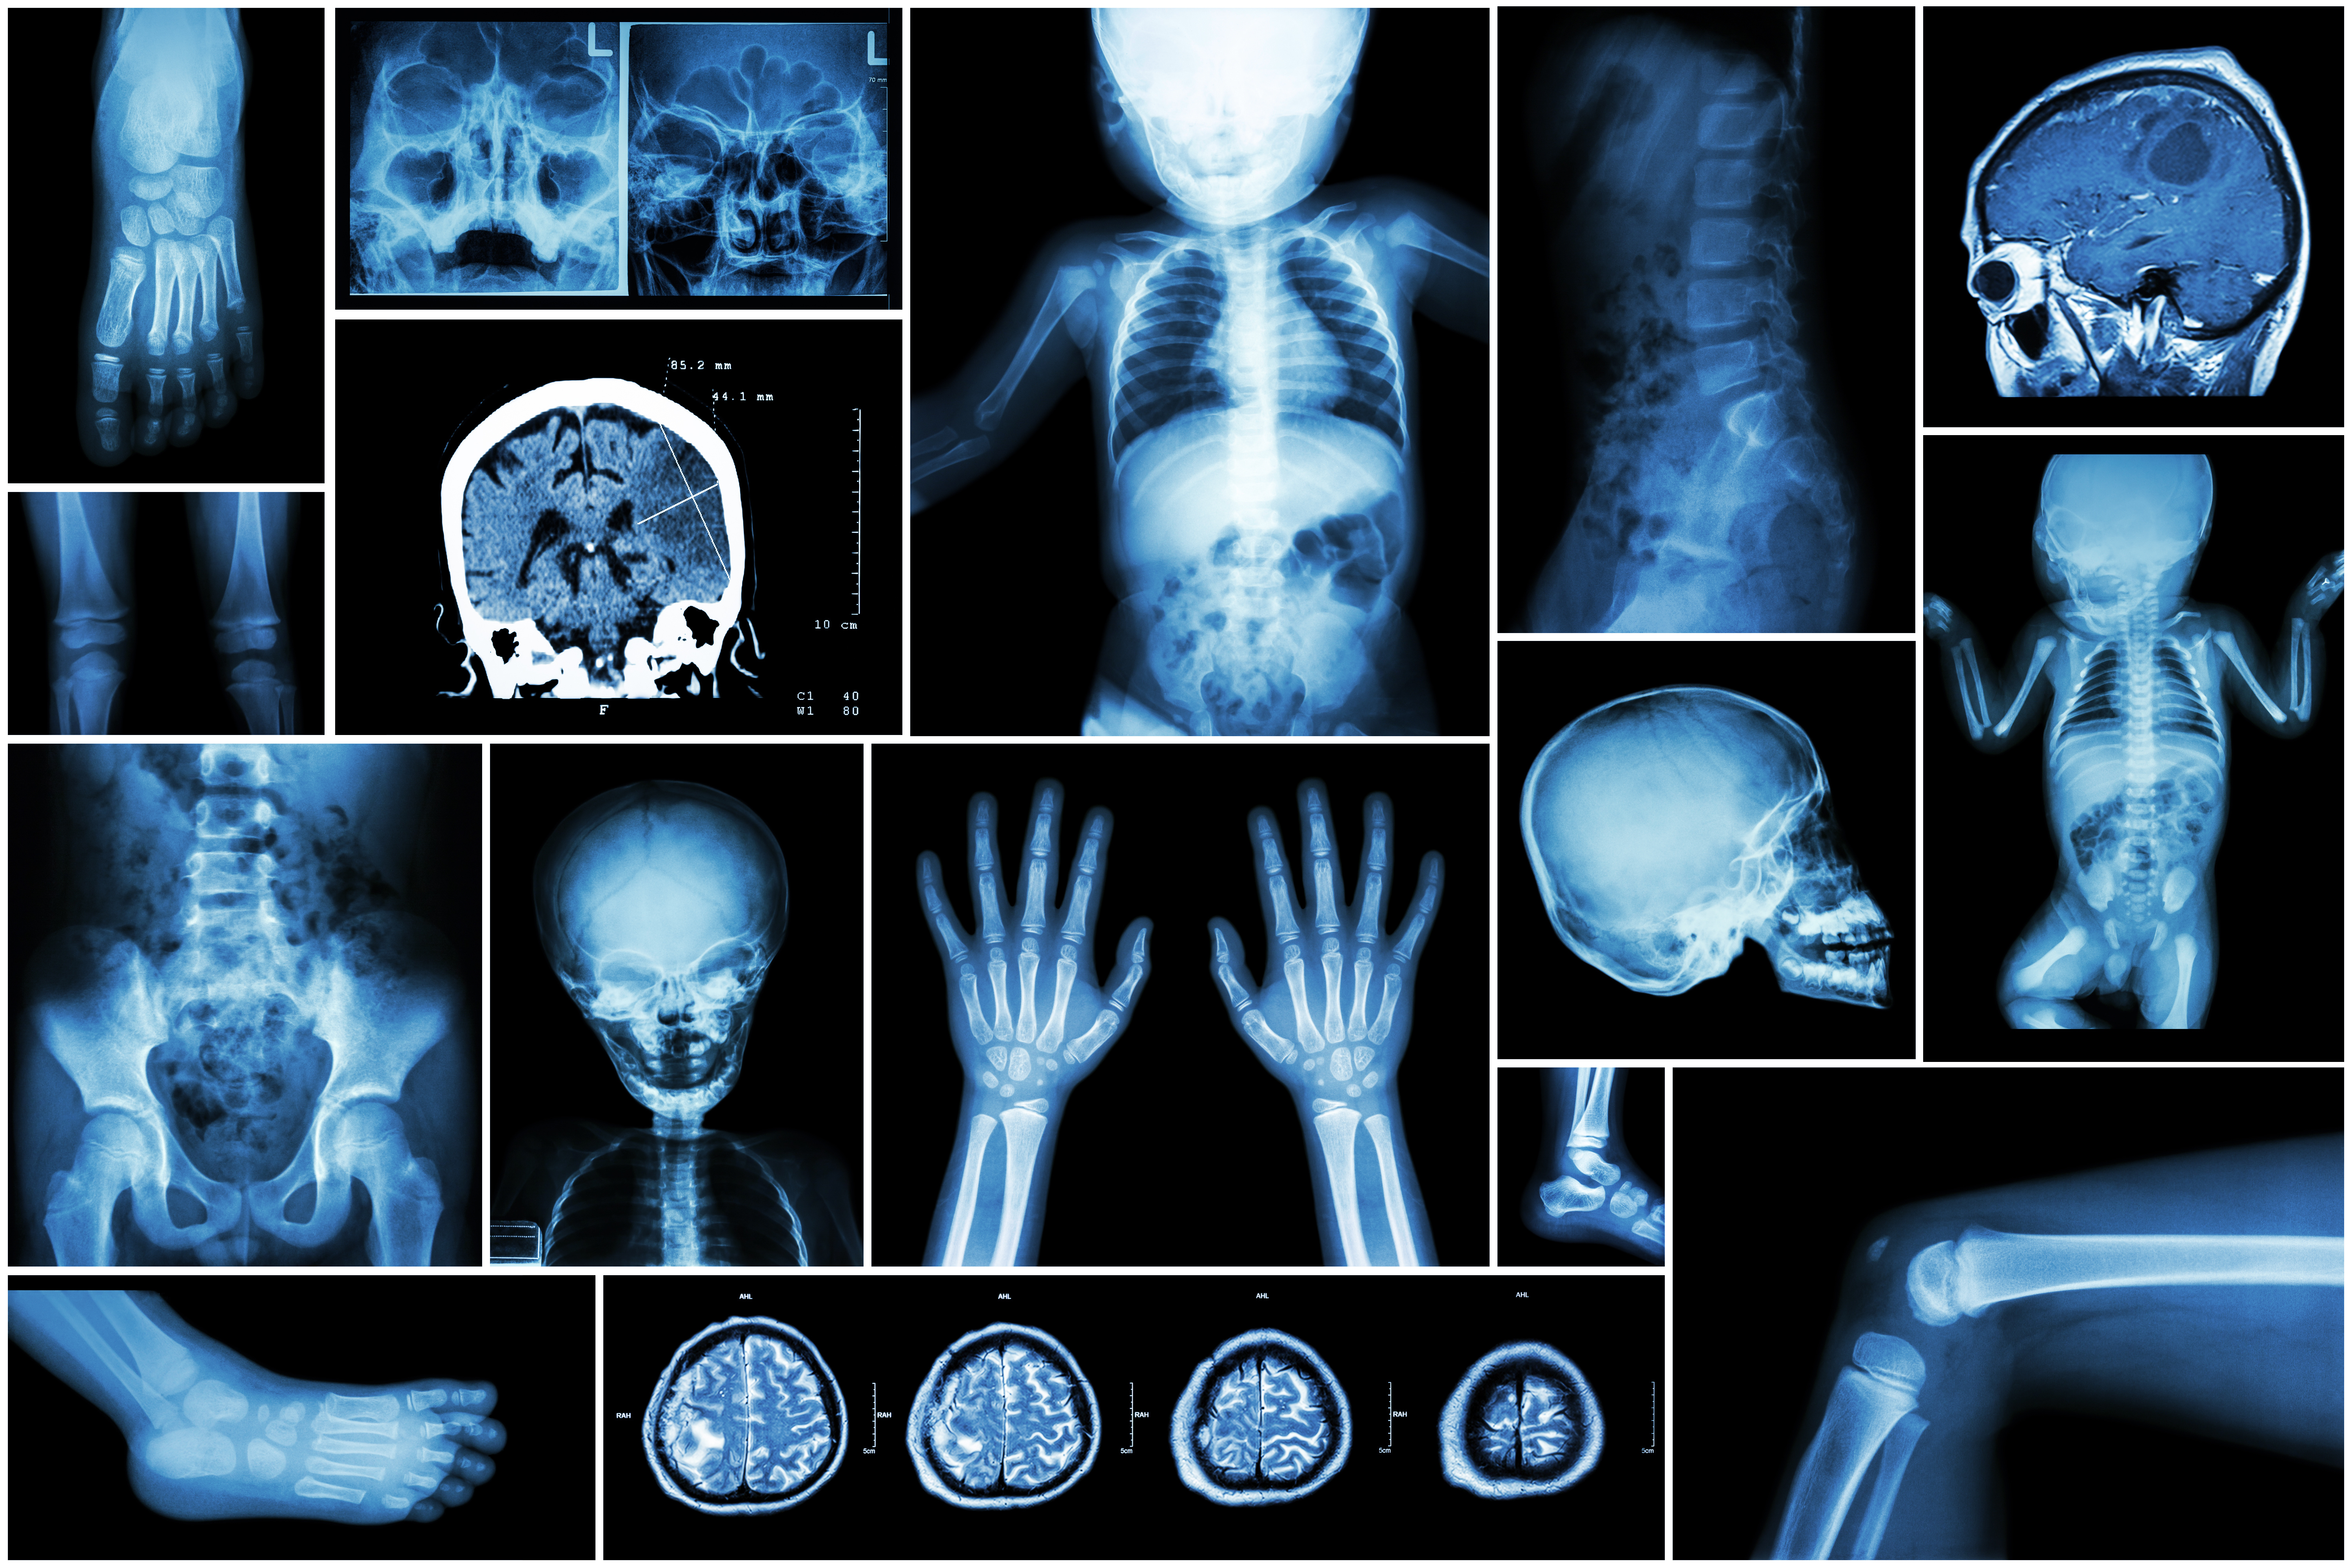

Https www i3 journal org highlights postmortem fetal magnetic resonance imaging attachment x ray multiple part of child s body multiple disease stroke brain tumor rheumatoid arthritis sinusitis gouty arthritis etc skull chest lung heart spine arm hand pelvis leg knee fo (फाइल का प्रकार jpg)

X Ray Multiple Part Of Child S Body Multiple Disease Stroke Brain Tumor Rheumatoid Arthritis Sinusitis Gouty Arthritis Etc Skull Chest Lung Heart Spine Arm Hand